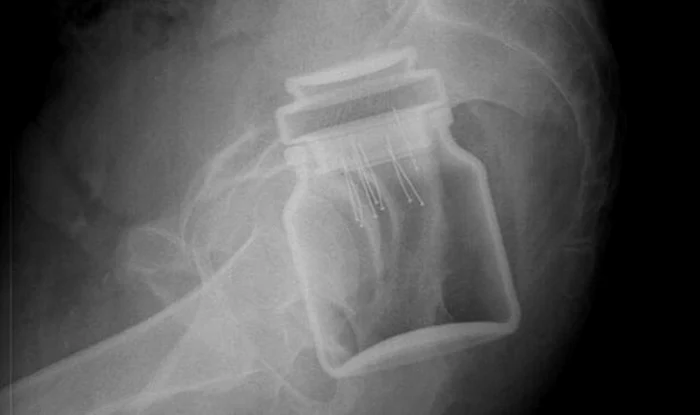

”Iniţial am crezut că glumeşte. La o examinare sumară se putea vedea că este vorba de un corp străin, însă nu am crezut că ar fi chiar un pahar. A fost trimis la o radiografie, iar rezultatul ne-a lăsat mască pe toţi. Era un pahar cu gura în jos”, și-a amintit pentru monitorulbt.ro, un medic din cadrul Unităţii de Primiri Urgenţe ce s-a întâmplat acum un an. Nimeni nu s-a gândit însă cât de repede vor revedea pacientul. Pe 18 mai o salvare îl aducea pe bărbat din nou la Unitatea de Primiri Urgențe a spitalului.”Este vorba de un pacient cu un corp străin anal şi rectal. Un borcan de sticlă”, a fost constatarea personalului medical din cadrul UPU-SMURD. Cadrele medicale de la camera de gardă, aflate în priză pentru a depista bolnavii de coronavirus nu au recunoscut pacientul. Acesta a auzit însă o discuție pe această temă între mai multe cadre medicale și a anunțat senin că el este subiectul povestirii.”Pacientul se afla la baie, unde era pregătit pentru internare, pentru a fi supus unei intervenţii chirurgicale de urgenţă. Personalul de la baie vorbea şi îşi spuneau că acum un an fusese un bărbat cu un pahar în anus. Iar el, foarte dezinvolt, de pe targă, a ridicat mâna şi le-a spus: Eu sunt ăla!”, a povestit un cadru medical de la UPU pentru monitorulbt.ro

Dacă acum un an sticla din rectul pacientului a fost scoasă prin dilatarea zonei, de această dată personalul medical a preferat o operație.”S-a încercat scoaterea obiectului pe aceeaşi cale, însă a fost imposibil, existând pericolul de a se sparge în interior. Fiind vorba de o zonă puternic vascularizată, era pericolul unei hemoragii masive şi deces. Borcanul, la fel ca şi paharul de anul trecut, era blocat în zona rectului, astfel că s-a intrat chirurgical şi a fost scos prin abdomen”, a precizat un medic chirurg din cadrul Spitalului Judeţean de Urgenţă „Mavromati”.Ulterior, pacientul a fost internat pe secţia de reanimare, starea lui fiind bună. Bărbatul nu le-a spus cu exactitate medicilor motivul pentru care a recurs la gestul bizar şi extrem de periculos, acesta spunând doar că avea o mâncărime şi usturime de care a încercat astfel să scape.